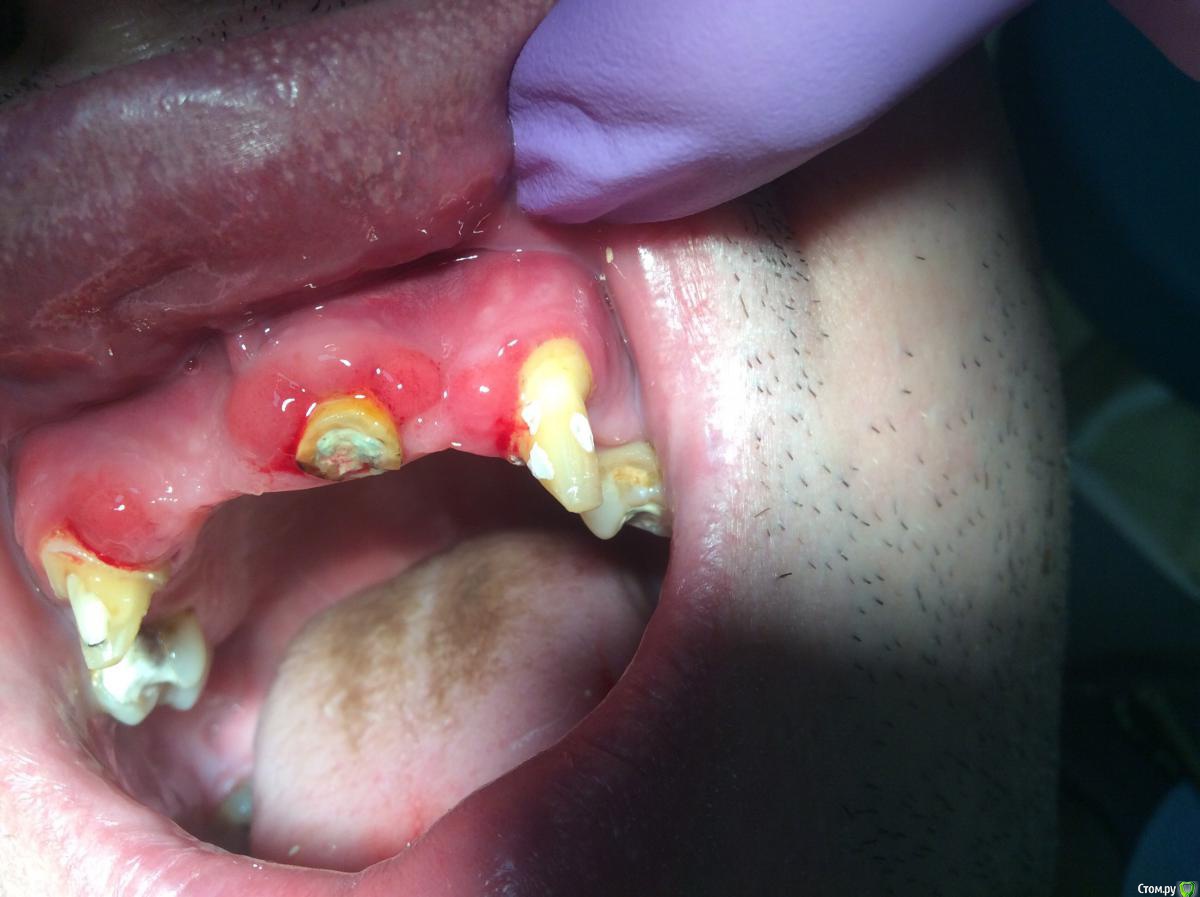

Neilrus Опубликовано 2 июля, 2015 Поделиться Опубликовано 2 июля, 2015 (изменено) Здравствуйте все.Ситуация для меня непонятная, но, возможно, кто-нибудь из вас сталкивался с подобным непроходящим локализованным хроническим гингивитом (гипертрофический?).Итак, по этапам: Была грязь во рту и просто жесть. Такая десна была везде, половину зубов было не видно. Волосатый язык. Корни. Жуткий псориаз на коже лица и волосиситой части головы. Что там ниже не смотрел. Первым делом направил на стандартные для такого случая анализы, все отрицательно. Сахар только все никак не может сдать утренний. Начали удалять. Удалили более 10 зубов на обеих челюстях. Во фронте стоял мк мост на 13-11-23 с обработкой просто под конус, такого еще не видел, то есть просто под конус, без уступов. Клыки витальные оказались. Пародонтальные зубо-десн карманы у каждого из этих трех зубов по 2-3 мм. Подвижность 1-2 степени, ближе к отсутствию патологической подвижности.Спустя месяц как мы начали хир санацию и терапевтическую у него почти полностью ушла чернота с языка, неприятный запах, гной, воспаление и прочее. Псориаз он начал лечить гормональными мазями какими-то, тут я не в курсе, дерматолог что-то прописал. Клыки я временно обработал с уступом для времяшек. Депульпировал. 21з - вытащил вкв кривую и распломбировал. И вот вопрос собственно: почему не уходит воспаление с фронтальной группы? Все почистили. Полоскаем. Мажем. Промывное хорошее. Ничего не давит нигде. Повторюсь, 13 и 23 были витальные, сейчас под каласептом. Периапикалтно ни у одного ничего страшного не обнаружил, разве что щель расширена.Прикус фиксирован за счет времянок, травма при окклюзии исключена. Может нужно отслойку сделать и корни полировать всем что есть? Вектора нет в клинике. Спасибо за советы. Изменено 2 июля, 2015 пользователем Neilrus Ссылка на комментарий